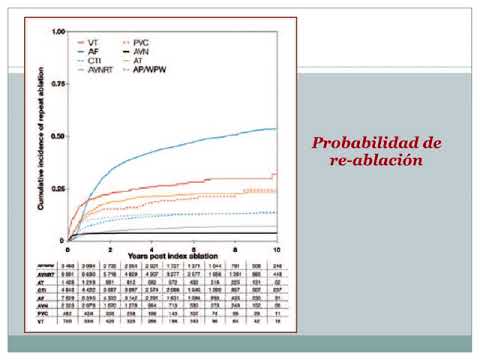

Una década de ablación de arritmias cardiacas en Suecia. Dra. Carolina Reynoso. Residencia de Cardiología. Hospital C. Argerich. Buenos Aires